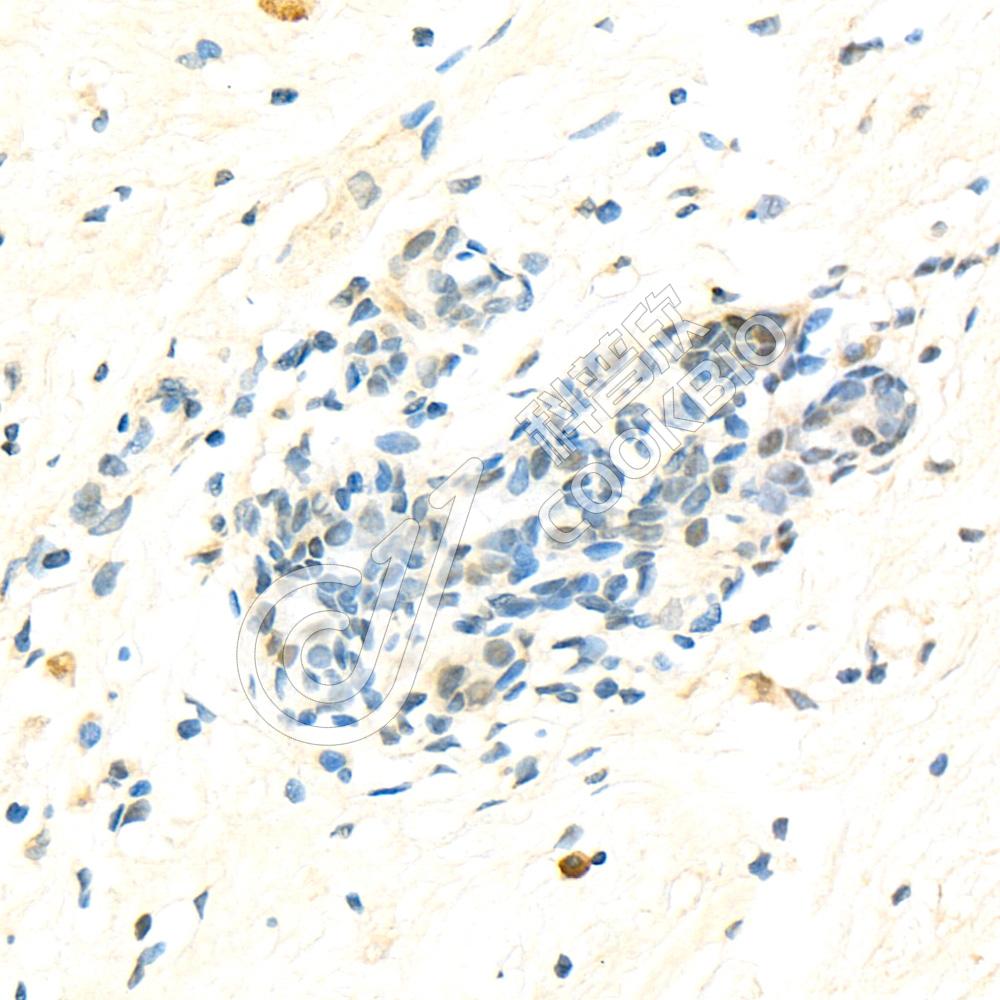

IHC检测Serum Response Factor SRF蛋白(货号 K1333144).

样品: 大鼠小肠, 4%多聚甲醛 (货号KSG1101) 固定12-24小时.

抗原修复: 柠檬酸抗原修复液(干粉, pH 6.0) (KSG1201), 98℃, 20分钟.

—抗: 1: 1800稀释, 4℃ 孵育过夜.

二抗: S-vision免疫组化多聚二抗(山羊抗兔),即用型 (货号KB3906), 室温孵育20分钟.